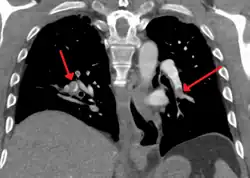

Example of a CTPA, demonstrating a saddle embolus. The white area above the center is the pulmonary artery, opacified by radiocontrast. Inside it, the grey matter is blood clot. The black areas on either side are the lungs, with around it the chest wall. | |

A normal CTPA scan will show the contrast filling the pulmonary vessels, appearing as bright white. Any mass filling defects, such as an embolus, will appear dark in place of the contrast, filling/blocking the space where blood should be flowing into the lungs.

On CTPA, the pulmonary vessels are filled with contrast, and appear white. Any mass filling defects (embolus or other matter such as fat) appears darker. Ideally, the scan should be complete before the contrast reaches the left side of the heart and the aorta, as this may mean contrast has drained from the pulmonary arteries, or require a larger dose of contrast media.[12]